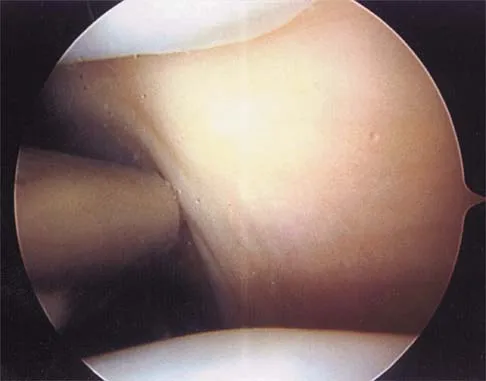

Figure 19 shows an arthroscopic view from the anterior lateral portal of the knee looking into the suprapatella pouch. The use of an electrothermal device during this procedure most commonly causes significant postoperative complications by damaging which of the following structures?

Explanation